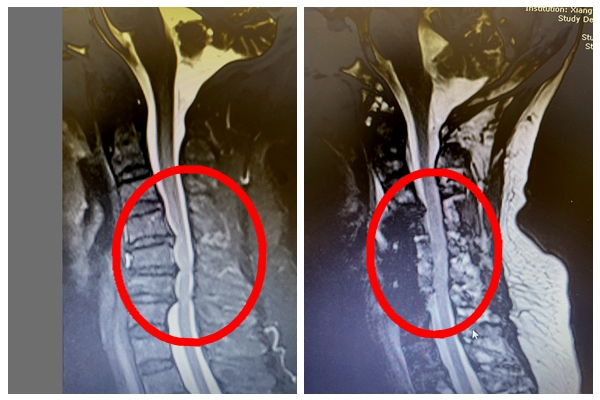

近日,67岁的金女士干农活时因头晕摔倒在地,昏迷了半小时后才逐步清醒。醒后便感觉四肢麻木、活动受限,金女士用仅能稍稍活动的一根手指拨打了求救电话。家人知晓后立即将金女士送往当...